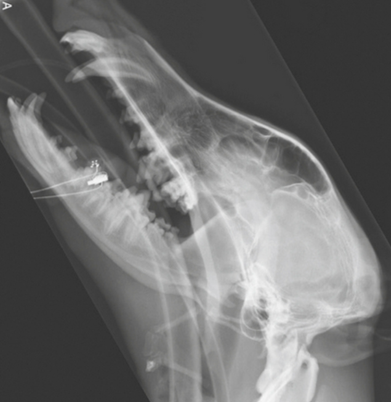

15

Q

A

fractured mandibula in oblique views

in the right mandibula view you can barely see the fracture due to superimposition of structures so capture both mandibula on their own image.